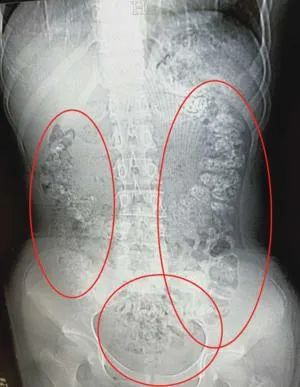

14岁女孩小沈在喝了一段时间珍珠奶茶后5天没有排便,肚子也疼,吃不下东西,于是在父母陪同下到浙江诸暨市人民医院急诊就医。

CT检查后发现,小沈的胃肠内布满一颗颗圆的高密度阴影,全是没有消化完的“珍珠”。

诸暨市人民医院急诊科主任何玉领解释说,奶茶中的“珍珠”是木薯淀粉做成的,是不易消化的食物,有的商家还会加入增稠剂等添加剂,如果连续大量食用,很容易导致胃肠功能紊乱。